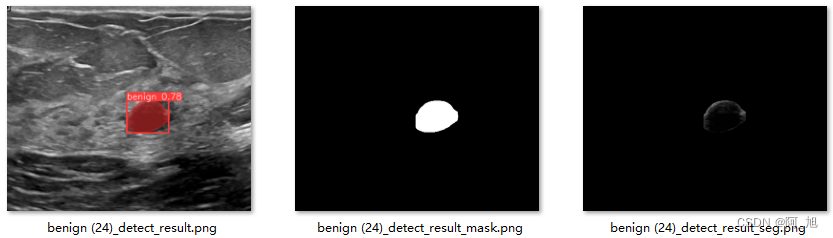

点击保存按钮,会对图片的检测结果进行保存,共会保存3种类型结果,分别是:检测分割结果标识图片、分割的Mask图片以及原图分割后的图片。存储在save_data目录下,保存结果如下:

执行上述代码后,会将执行的结果直接标注在图片上,结果如下: